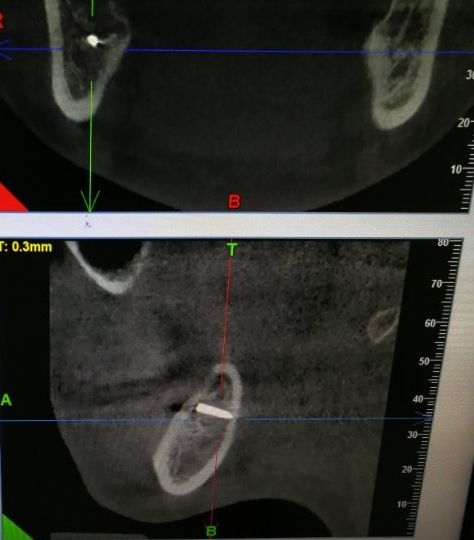

李女士口腔内的金属物。这一检查,把她吓了一跳。据其在松岗人民医院口腔科拍摄的x光片显示:她之前拔掉的智齿牙窝里,残留了两节金属物,并且已经没入很深,快要接近下颌神经管了。如果再深一点,可能会导致其面部神经损坏。“我听到,差点吓哭了。”李女士说。自己当时因为想省点钱,就去了小诊所,没想到竟然发生了这样的事情。好在后来去医院还算及时,医护人员确定位置和异物大小等情况后,利用超声骨刀把李女士牙窝中的异物取了出来。后经十余天的输液治疗,李女士的情况已经基本恢复。

取出的金属物长约1公分。那么,嵌入李女士牙窝中的金属物质到底是什么呢?松岗人民医院口腔科医生石健介绍,医院接诊后,为患者拍摄了X光片。从X光片能够看到,李女士拔牙创口有一个密度很高的金属影,长度约1公分。经联系李女士拔牙的诊所医生了解到,这个异物可能是拔牙用具“压挺”的尖端碎片。“牙挺是靠撬力来拔出牙齿的,医生如果用力不当,有时会将牙挺尖端折断,遗留在患者的牙窝内。”石健医生说。据介绍,因异物嵌入很深,快要接近神经管,取出时风险较大。后经商议,决定使用超声骨刀帮患者将异物取出。李女士表介绍,事发后,当时为其拔牙的小诊所对此进行了道歉和赔偿。